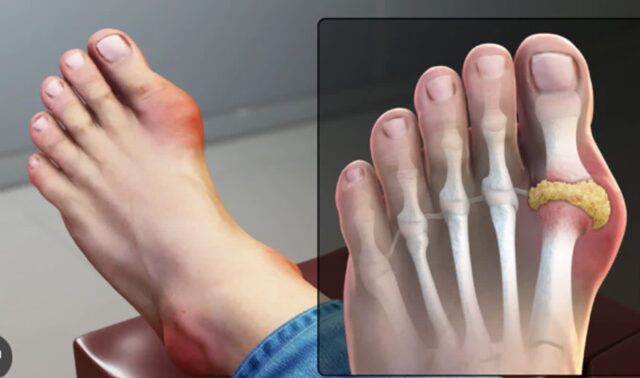

엄지발톱 염증 원인 및 증상 조갑주위염 손발톱 주위 감염, 내성발톱 으로 인해서, 치료 및 관리 방법